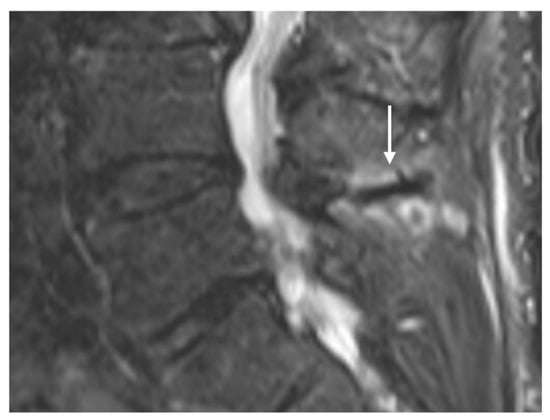

Osteoid osteomas (OOs) account for 10–14% of primary vertebral tumours. The majority are seen in the lumbar spine, followed by the cervical and thoracic spine. Given their predilection for the posterior elements, involvement of the spinous process is not uncommon [15,16]. MRI is sensitive and may show marrow oedema; however, the oedema can obscure the nidus, which can be a potential pitfall. On MRI, the nidus when seen is of low to intermediate T1 signal, ofvariable T2 signal with areas of signal void due to mineralisation (Figure 2a). The nidus may also show variable enhancement on post-contrast imaging [15,16]. Lesions may be occult on a radiograph. The presence of sclerotic reactive bone surrounding a lucent nidus is a typical feature on CT, although the latter may not always be present (Figure 2b). A central sclerotic dot may also be present. The nidus is typically <1.5 to 2 cm in diameter.

Figure 2.

Sagittal STIR (a) and CT (b) images demonstrating a thoracic spinous process osteoid osteoma (white arrows). Note the presence of reactive marrow oedema on the STIR sequence. The sclerotic reactive bone is well delineated on CT, although the lucent nidus may not always be present as in this case.